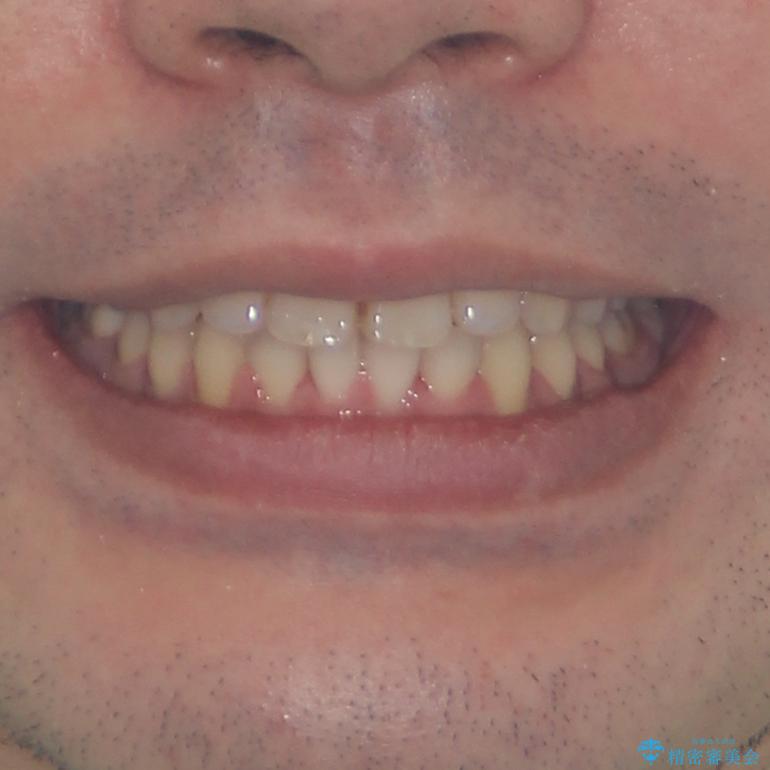

- 前歯のデコボコを治したいとのことで来院された患者様です。

できる限り楽して、短期間で治したいとのことで、ワイヤー装置にて矯正治療を行うこととしました。

- メタルブラケット